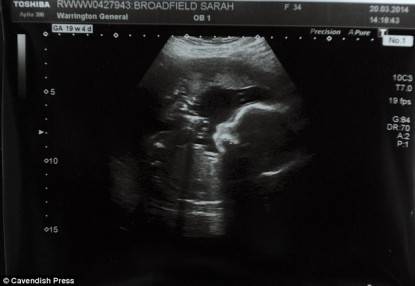

Purtroppo un’ecografia successiva ha mostrato che uno dei feti era stato abortito.

“I medici ci hanno assistito con un occhio di riguardo, ma nonostante ciò avevo i nervi a pezzi prima di ogni ecografia, in attesa di brutte notizie” dichiara Sarah.